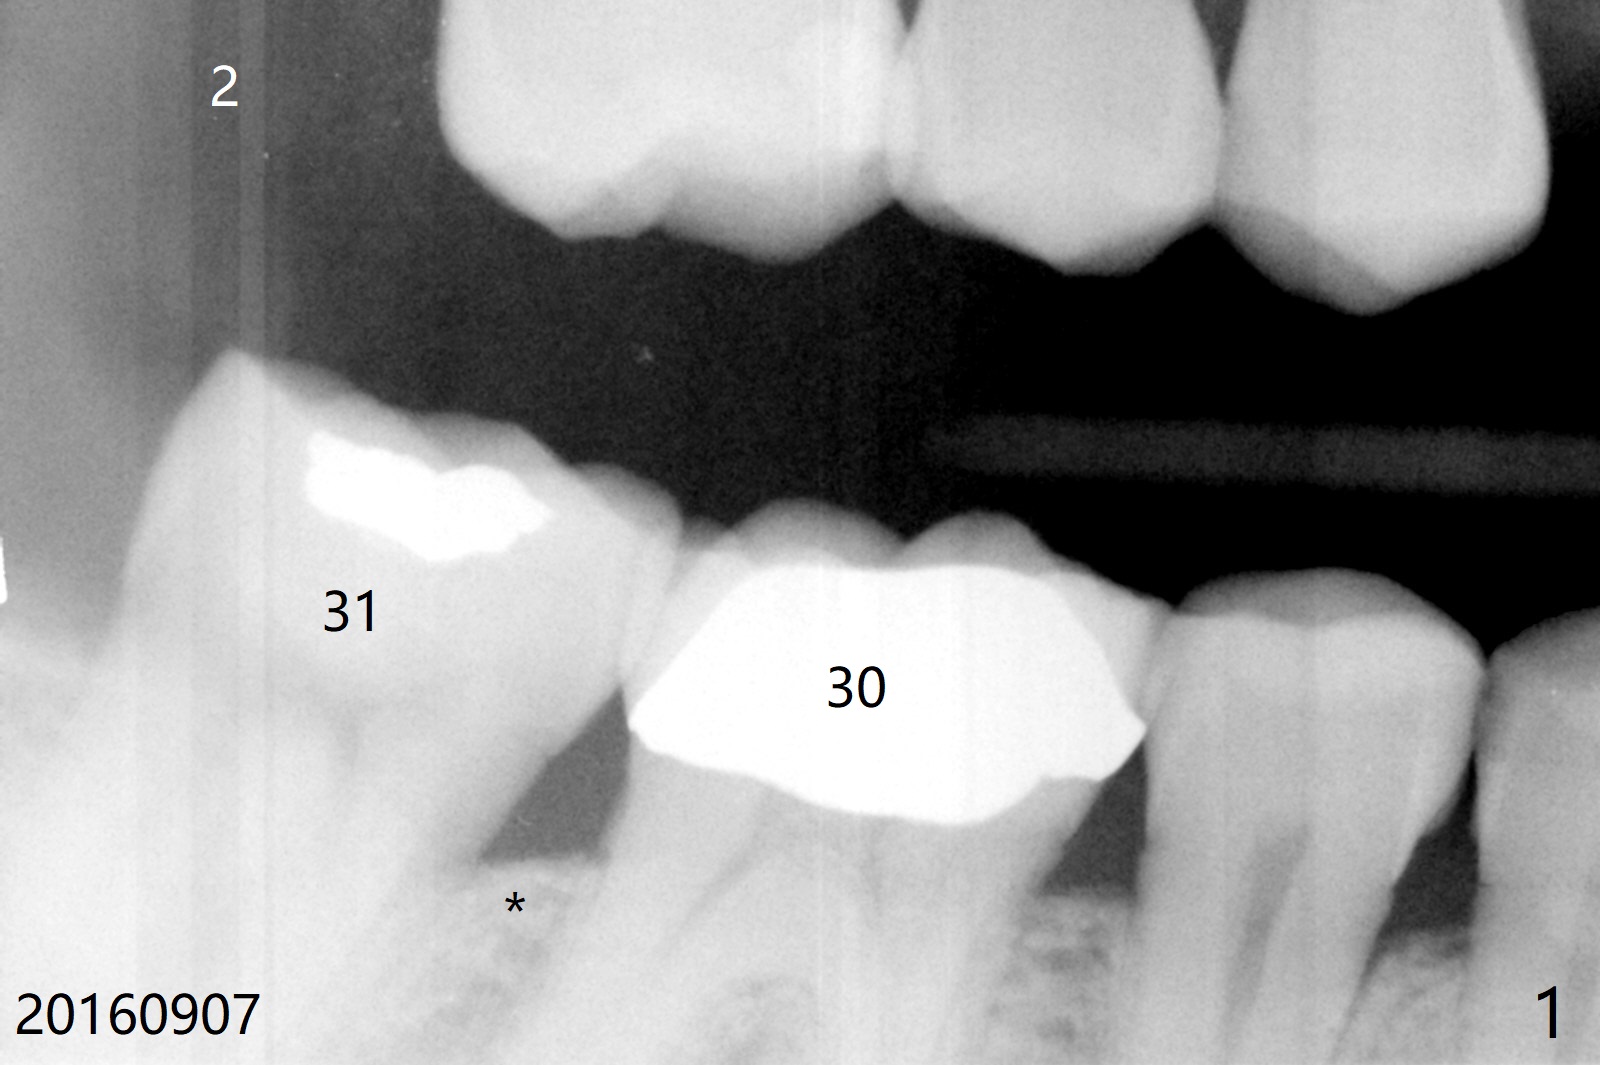

A 71-year-old man finally agrees to have an implant to be placed at #2 four years being our patient. The break point is that the crown at #30 needs recementation. The tooth #2 was missing when he presented for new patient exam (Fig.1,2). The bone loss between #30 and 31 is mild (Fig.1 *) with a small diastema (Fig.2 >). Porcelain chips at the pontic (Fig.3 >). The bone height at #2 is limited (Fig.4). The bone loss and the diastema seem to have got worse in the last 3-4 years (Fig.5). The tooth #15 has mobility with exposure of the buccal roots (Fig.6). Because of bruxism, consider flap surgery to bury the implant at #2 with guide.